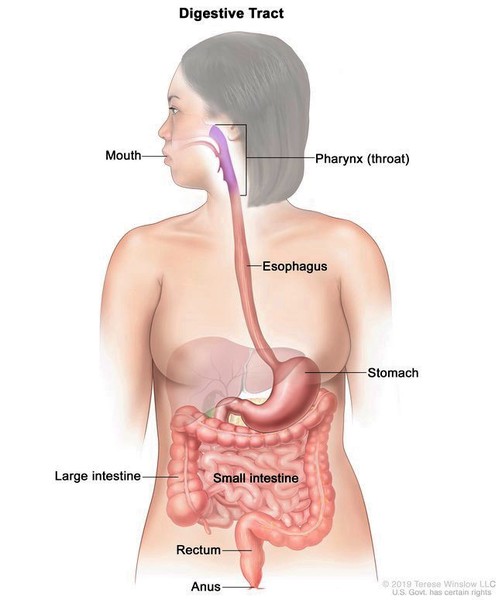

List showcases captivating images of what is on the right side of female body galleryz.online

what is on the right side of female body

We extend our gratitude for your readership of the article about

what is on the right side of female body at

galleryz.online . We encourage you to leave your feedback, and there’s a treasure trove of related articles waiting for you below. We hope they will be of interest and provide valuable information for you.